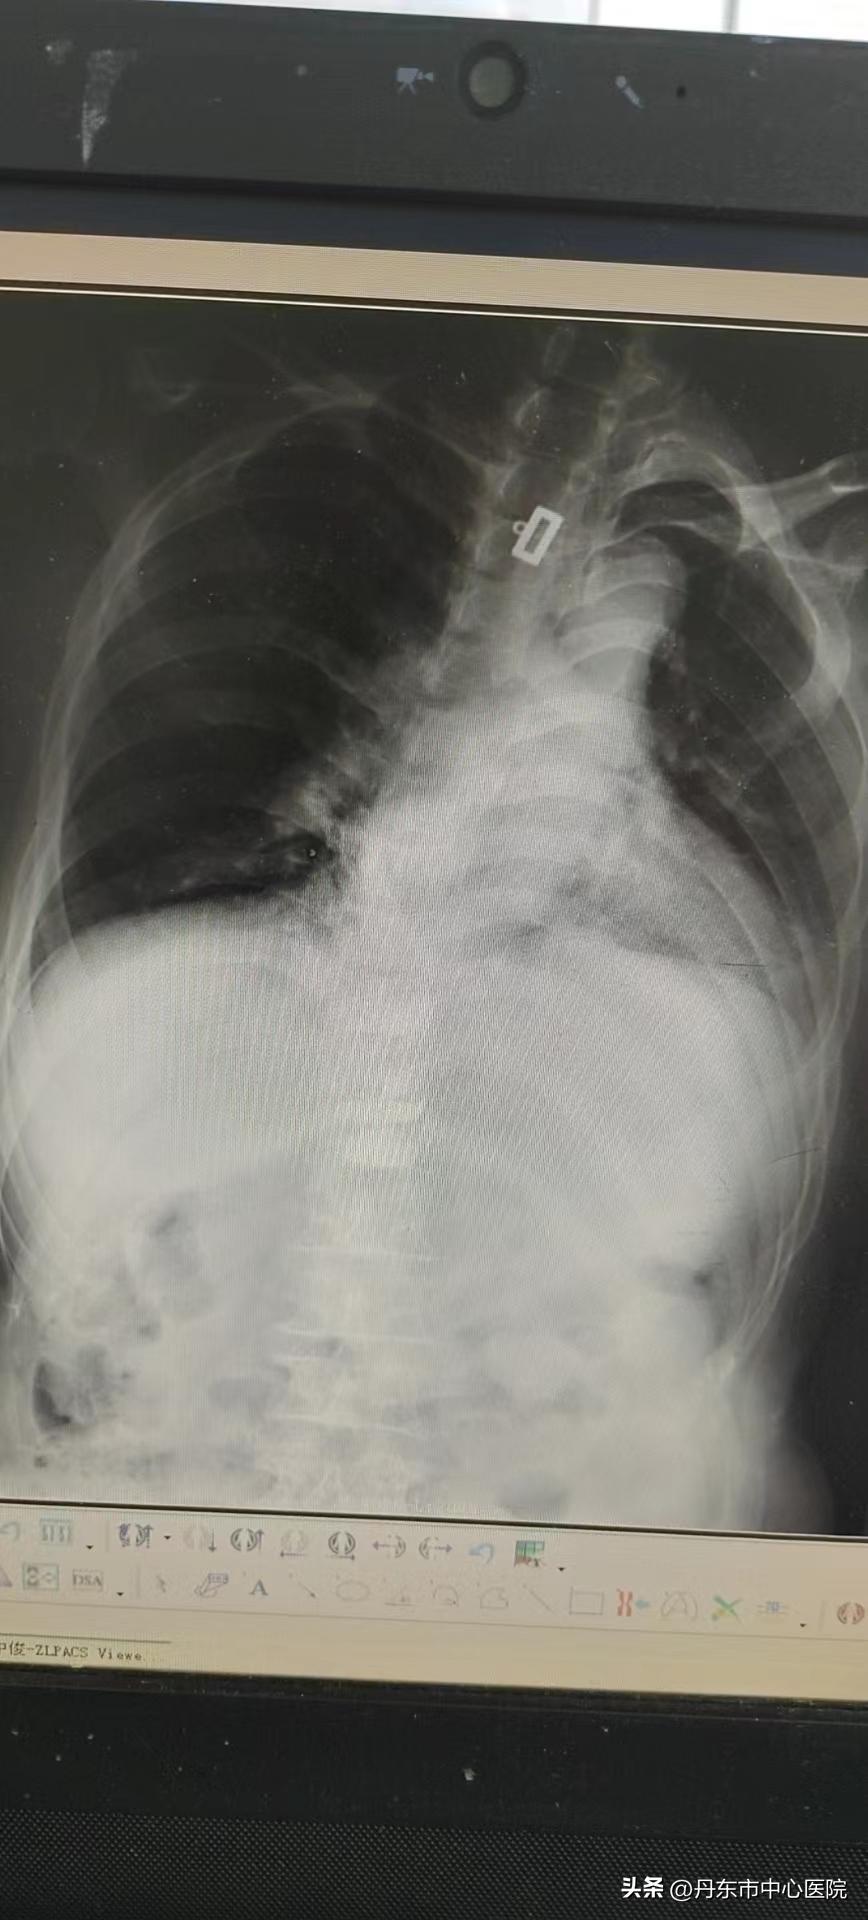

患者术后DR

术后DR显示,骨水泥置入位置良好,患者无不良反应,患者疼痛和活动受限得到良好改善。